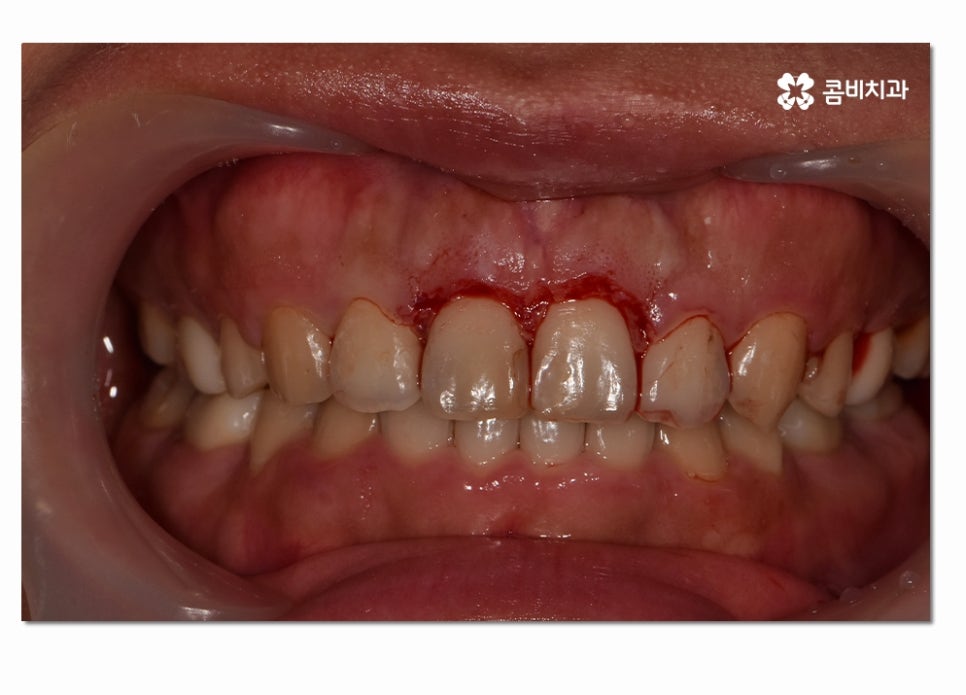

수술적인 치료 방법은 치은절제술과 치은성형술,치주판막술,치주성형술 등을

예로 들 수 있으며 오늘 소개 드리고자 하는 케이스는

치은절제술에 해당하는 치료 방법으로 너무 늦지 않게 치료하여

잇몸과 치아를 건강하게 살린 케이스라고 말씀드릴 수 있어요.

이러한 수술적인 방법은 잇몸을 절개하고 치은 깊숙하게 숨어 있는

치석을 제거해 주거나 치주조직이 다시 건강하게

회복될 수 있도록 형태를 바꿔주며 재생을 돕는 방법이라 할 수 있는데요.

본 글은 콤비치과의 의료광고 포스팅이며

개인에 따라 출혈 및 부작용이 발생할 수 있습니다.